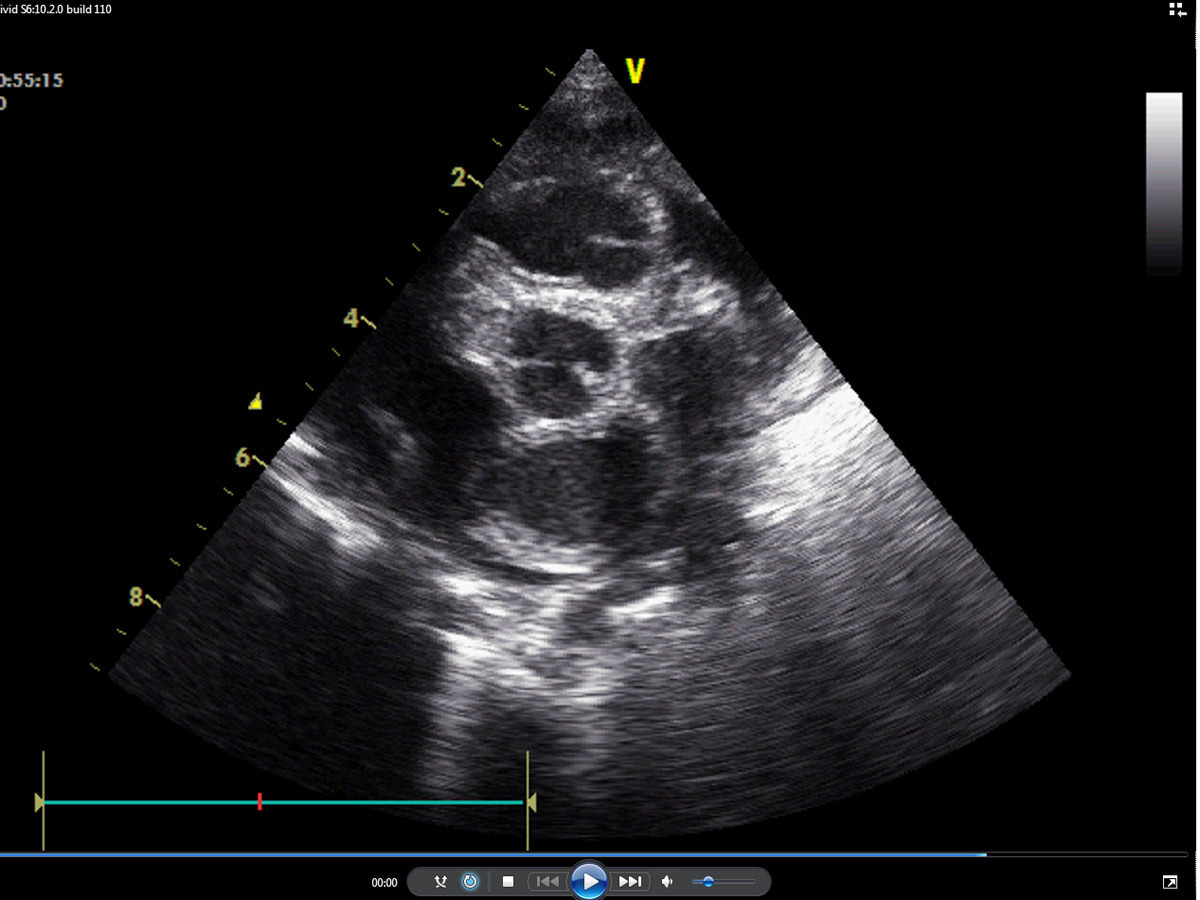

Certaines cardiopathies ne soufflent pas, d’autres soufflent plus tardivement (communication interventriculaire [CIV] par exemple).